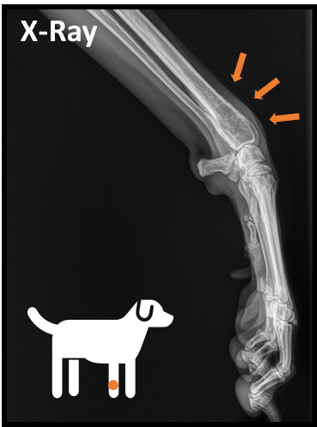

Osteosarcoma X-Ray

Assessing the Effects of Histotripsy on Osteosarcoma Tumor-Affected Bone

Motivation: Histotripsy is a novel cancer treatment which has been used to mechanically ablate primary osteosarcoma tumors, but whether bone tissue is compromised has yet to be analyzed (Work of Preeya Achari)

Goal: Determine the effect of histotripsy on the mechanical integrity of treated bone in murine and canine models using real-world compression testing and computational Finite Element Analysis to validate further exploration into histotripsy as a safe treatment alternative for osteosarcoma.